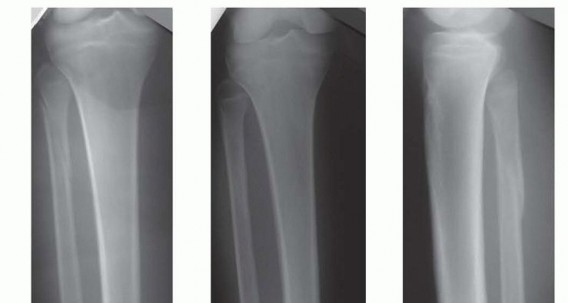

### FIG 1 • A. The metaphyseal segment extends with knee flexion secondary to the pull of the patellar tendon. B. The anterior tibial crest is palpable and represents the vertical lateral border of the tibia. Palpation of the crest can help aid in starting wire orientation. C. Anterior neurovascular structures are at risk during anterior placement of distal interlocking bolts; internal rotation may decrease the risk of arterial injury. A detailed neurovascular examination is critical to avoid the devastating complications associated with compartment syndrome, which can occur in both closed and open fractures (see Cha 53). ## IMAGING AND OTHER DIAGNOSTIC STUDIES Full-length anteroposterior (AP) and lateral plain radiographs are necessary to adequately evaluate the tibia and fibula. Complete orthogonal views of the tibia and fibula help evaluate for concurrent fractures or dislocation and any preexisting deformity or implants. Orthogonal radiographic views of the knee and ankle are required to rule out articular involvement. Axial computed tomography (CT) scan can be used for proximal and distal fractures to rule out intra-articular fracture extension. Nondisplaced fracture lines are common. Gunshot wounds may merit CT evaluation to rule out intra-articular bullet fragments and intra-articular fracture extension. Magnetic resonance imaging (MRI) is not useful for most diaphyseal or metadiaphyseal fractures. Ankle-brachial index (systolic pressure in injured leg below injury divided by systolic pressure of the brachium) after fracture reduction should be used to rule out vascular injuries in severely displaced fractures or fractures with severe soft tissue injury. Values of less than 0.9 may be indicative of vascular injury, requiring further investigation. 18 549 Compartment pressure evaluation with a commercially available handheld single-stick monitor or with a sideported catheter connected to a pressure monitor (using the arterial line setup) is indicated in patients who have severe or increasing swelling and are not able to comply with physical examination and questioning. Observe for early signs of compartment syndrome in all patients with tibial diaphyseal fractures. Open fracture does not preclude development of compartment syndrome. Measure the pressure difference between the diastolic pressure and the intracompartmental pressure—a differential value of less than 30 mm Hg is considered an indication for a four-compartment fasciotomy. 17 ## NONOPERATIVE MANAGEMENT Nonoperative management is indicated in ambulatory patients for closed and open fractures that do not require flap coverage and that do not present with excessive initial shortening or unacceptable angulation when a cast is applied ( FIG 2). An intact fibula with an axially unstable fracture pattern (ie, short oblique, butterfly fragment, or comminuted) is at risk for shortening and varus deformities and is a relative contraindication to nonoperative management. A higher rate of malunion and nonunion with nonoperative management is seen in higher energy fractures. 2, 9 Joint stiffness, especially hindfoot, is common with all forms of prolonged immobilization. 7, 22 Initial treatment includes ˜2 weeks of a long-leg splint, then a long-leg cast for 2 to 4 weeks. When the initial swelling has subsided, the patient is graduated to a patellar tendon or functional brace. Weight bearing is allowed and encouraged.

### FIG 2 • A-C. An oblique diaphyseal tibial shaft fracture treated nonoperatively to union. (Courtesy of Paul Tornetta III, MD.) Radiographs are evaluated at 1- to 2-week intervals over the first month of treatment to confirm maintenance of acceptable alignment. ## SURGICAL MANAGEMENT